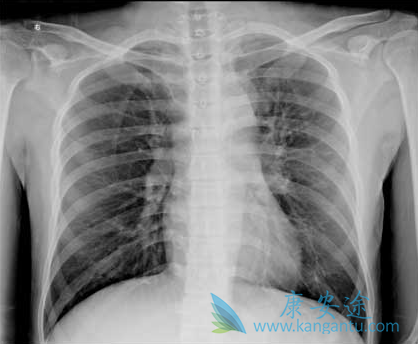

PD-1有望成为晚期肺癌治疗首选方案

6月16号, 默沙东公司宣布了一项重要的三期临床试验Keynote-024的新进展:在PD-L1高表达的非小细胞肺癌患者中,使用Keytruda的患者在无进展生存期和总生存期方面均比使用化疗的有显著的优势。也就是说:对于PD-L1高表达的晚期肺癌患者,一线治疗使用Keytruda比化疗活得长,活得好。

晚期肺癌治疗

Keytruda联合化疗用于肺腺癌有效率71%,这是今年ASCO年会刚刚公布的小临床数据,招募未曾化疗的非小肺癌患者,没有EGFR和ALK突变,所以没有使用相应的靶向药治疗。一共招募75名患者,分成三组,分别使用Keytruda联合化疗或者贝伐单抗治疗。C组招募非鳞的非小肺癌患者,接受Keytruda联合卡铂和培美曲塞,24名患者17位肿瘤缩小至少30%,客观有效率71%,无进展生存期10个月。

凭借比较好的二期临床数据,罗氏的PD-L1抗体Tecentriq已经上市。Tecentriq针对晚期肺癌的不少临床数据也已经公布。2015年ASCO公布了罗氏的PD-L1抗体Tecentriq联合化疗的1b临床数据,招募37位患者,接受Tecentriq联合卡铂+紫杉醇或者卡铂 +培美曲塞或者卡铂+蛋白结合型紫杉醇,总的有效率是67%,最重要的是发现有效率和PD-L1表达没有关系。PD-1/PD-L1抗体对晚期肺癌治疗带来新希望。